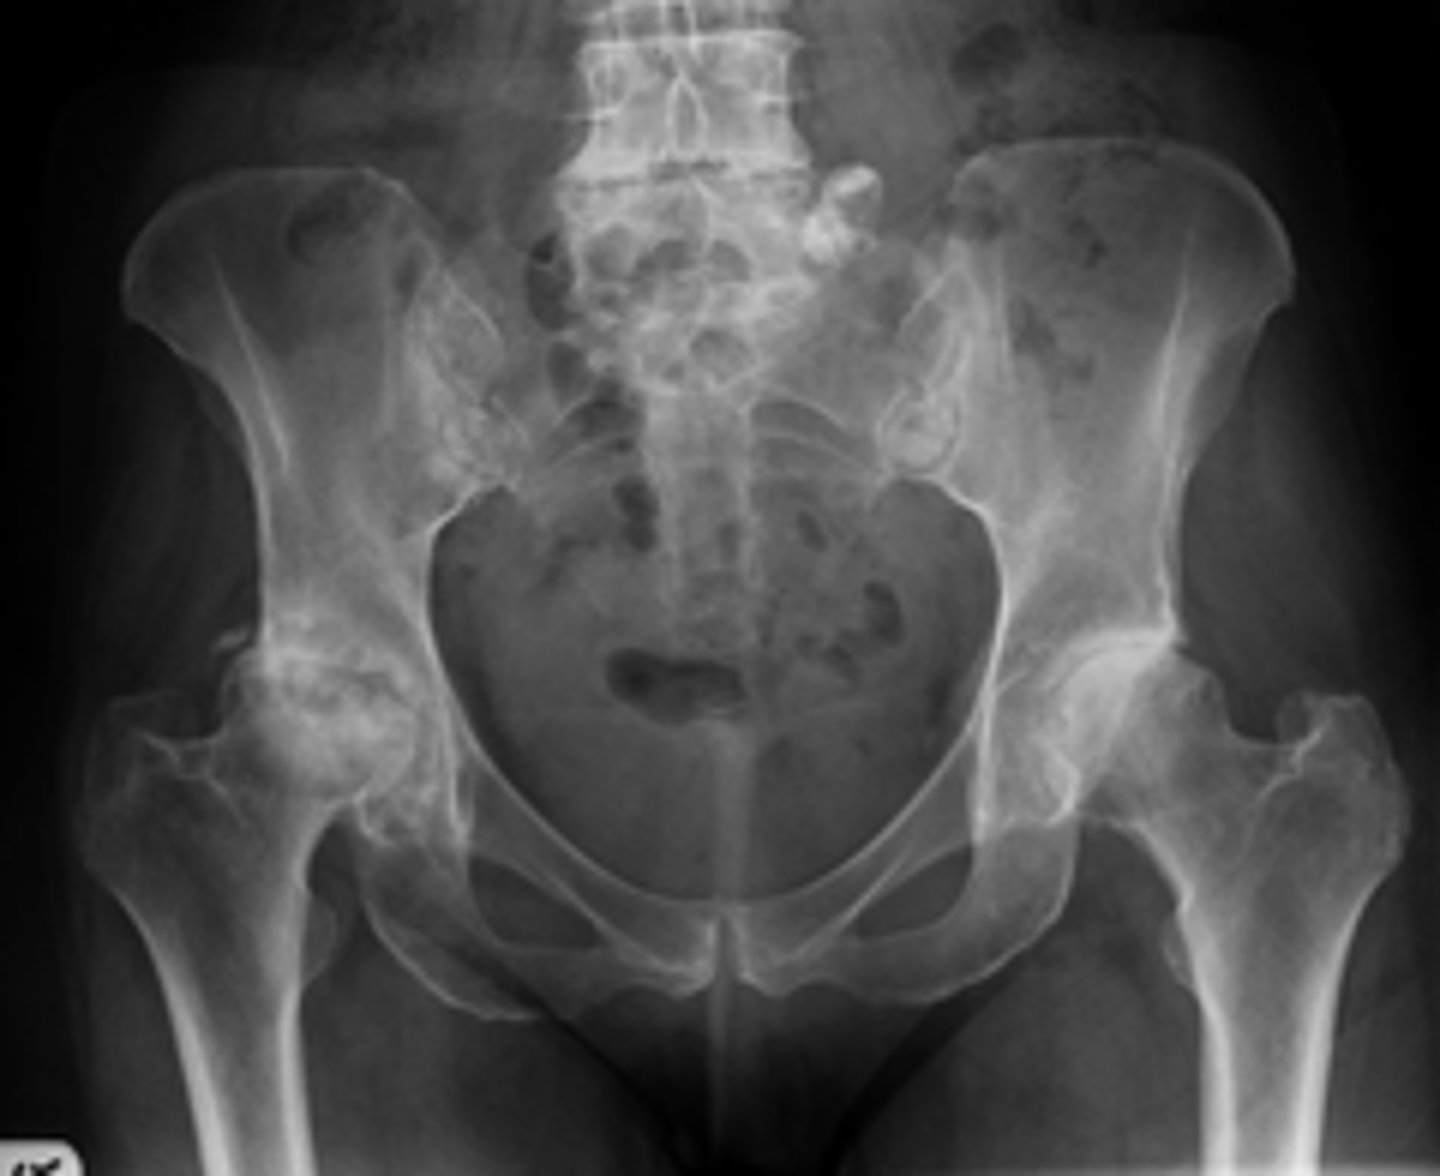

- CAM deformity

- Yes

- What "deformity" of the femoroacetabular joint is present?

- Do you think it relates to the diagnosis?

No

Would you adjust this patient?